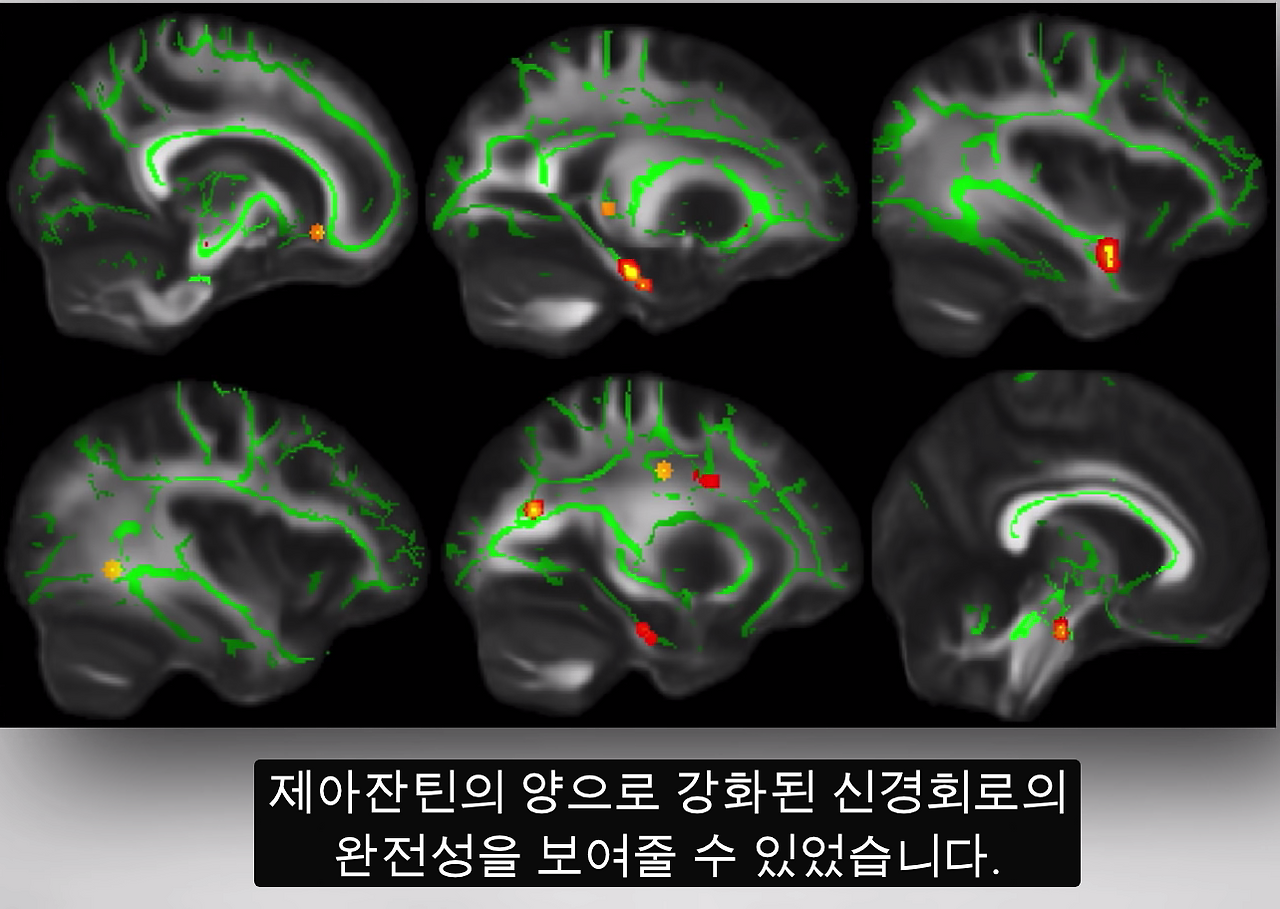

이렇게 우리는 살아있는 사람들을 대상으로 식이조절이 뇌 속 루테인 레벨을 반영하는 눈의 루테인 레벨에 영향을 줄 수 있는지를 관찰한 뒤에 이것이 인지 기능의 향상과 관련이 있는지 알 수 있습니다. 실제로 황반 색소(눈 속에 있는 루테인 같은 식물성 색소)의 양과 인지능력 검사 점수 사이에는 유의한 상관 관계가 있습니다. 우리는 루테인과 제아잔틴(zeaxanthin)이라는 식물 색소가 우리의 신경이 전달하는 신경 효율성을 향상시킴으로써 노년기에 인지 기능을 촉진한다는 사실을 f-MRI 스캔을 통해 입증할 수 있는데요. 확산텐서 영상(diffusion tensor imaging)을 사용해 백색질의 진실(white matter integrity)에 대해 연구한 멋진 연구를 살펴보면, 이는 뇌 네트워크 연결에 대한 유일한 인사이트(insight)을 제공하여 뇌 전체의 신경계를 따라갈 수 있도록 합니다. 연구자들은 사람들의 눈에서 관찰되는 루테인과 제아잔틴의 양으로 강화된 신경회로의 완전성을 보여줄 수 있었습니다. 특히 나이가 들면서 취약해지는 부위에 대해 우리 뇌의 통합성과 식단 사이에 유의미있는 관계가 있다는 증거입니다. 그렇다면 알츠하이머 환자는 이 황반 색소가 적을까요?